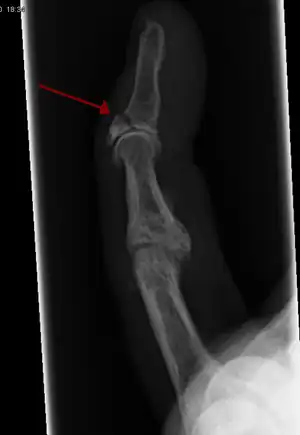

The diagnosis is generally based on symptoms and supported by X-rays.[3] The injury can be accompanied by swelling and ecchymosis.[6]

X-ray showing fracture at the insertion of the extensor tendon